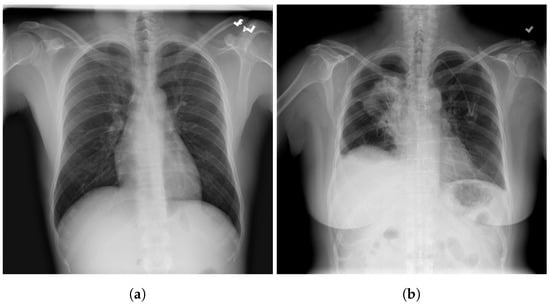

3.4. RSNA

3.5. Chest X-ray Images Pneumonia (CXRIP)